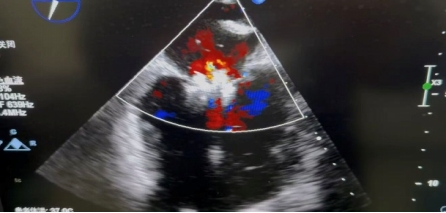

4.即刻驗證與釋放:鉗夾閉合后,食道超聲立即顯示:原先大量的二尖瓣反流顯著減少至輕度(反流面積降至3.1cm2),而瓣膜的開放未受嚴(yán)重影響,手術(shù)取得立竿見影的效果!確認(rèn)位置完美、效果達(dá)標(biāo)后,團(tuán)隊釋放了鉗夾器。

超聲顯示返流從大量降至微量

整個手術(shù)過程在團(tuán)隊的默契配合下,操作如行云流水。術(shù)后,患者安返病房,生命體征平穩(wěn)。三天后隨訪二尖瓣僅少量返流,肺動脈壓下降及三尖瓣返流明顯減少。